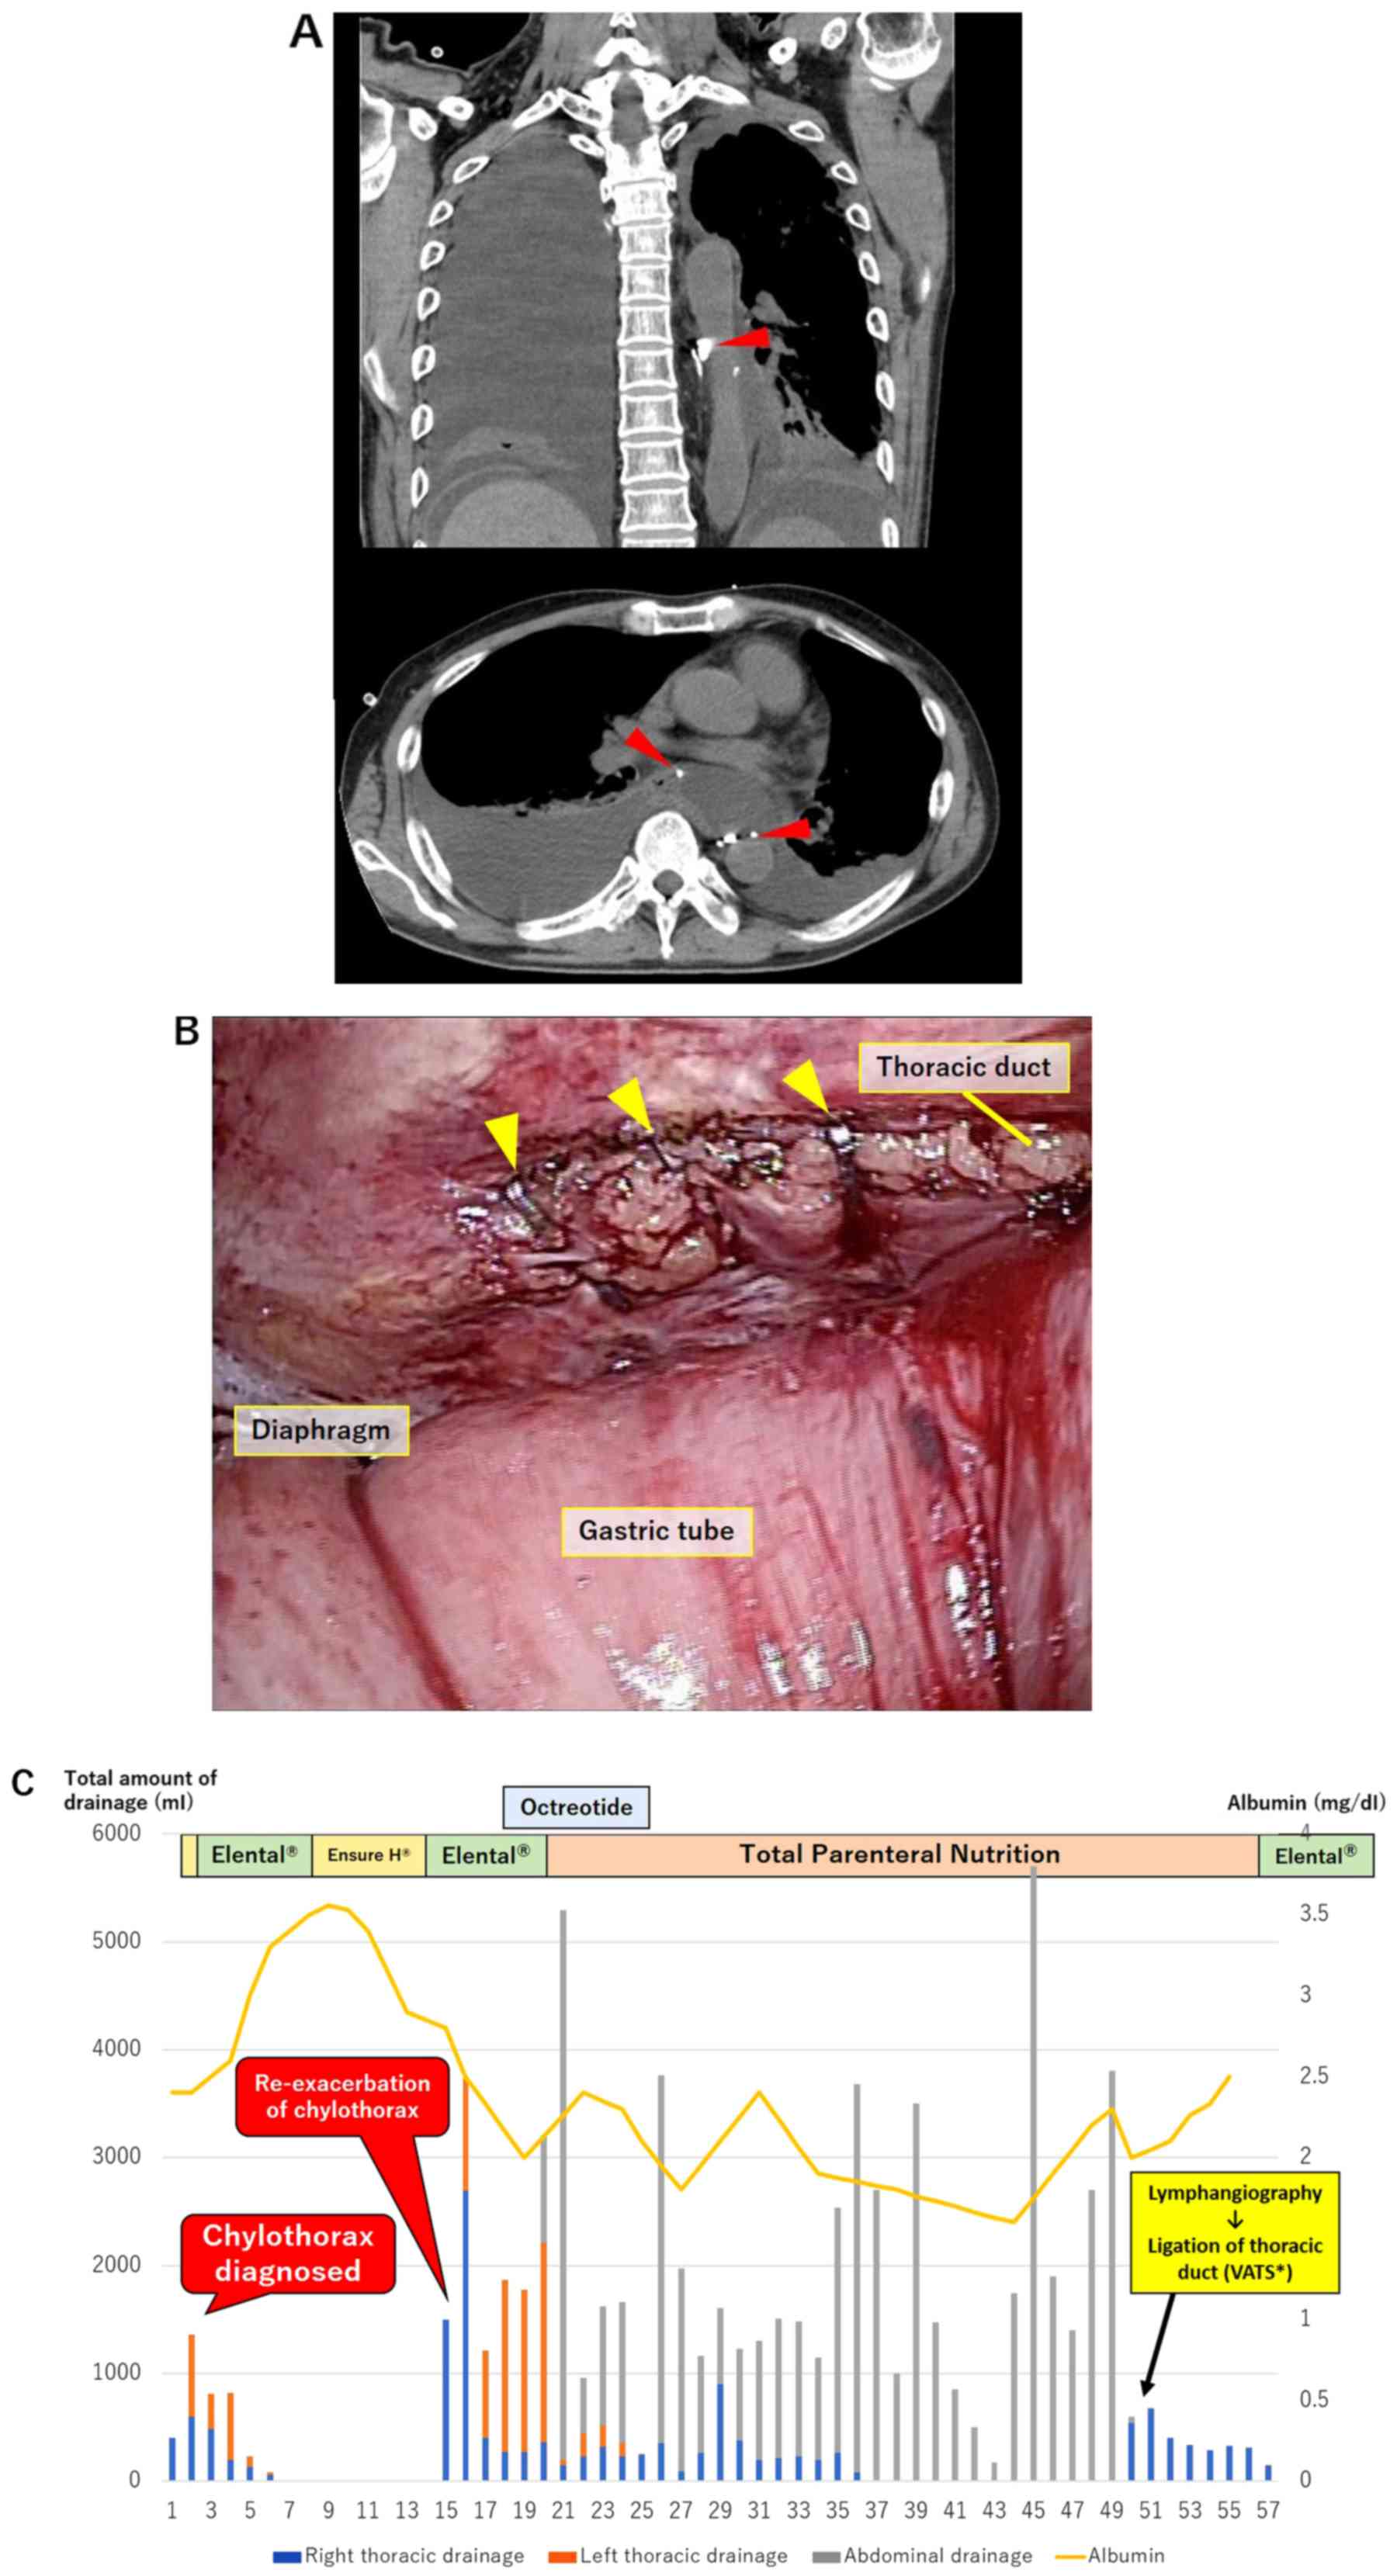

Figure 2.

(A) Representative computed tomography images of case 1: A contrast effect in the proximal side of the thoracic duct could not be confirmed. Movement of contrast medium to the right thoracic cavity was noted 4 cm on the caudal side of the tracheal bifurcation along the thoracic duct (red arrowheads). (B) Thoracic duct ligation performed under VATS in case 1. Esophagectomy with preserving the thoracic duct and gastric tube reconstruction via the posterior mediastinum was performed in previous surgery. The thoracic duct was identified cranial from the diaphragm and ligated with three clips (yellow arrowheads). (C) Clinical course of case 1. VATS, Video Assisted Thoracic Surgery.

A 67-year-old man was diagnosed as having middle thoracic esophageal squamous cell carcinoma of cT3N1M0 cStage IIIA (UICC 8th edition). He underwent radical esophagectomy by video-assisted thoracic surgery (VATS) following 2 cycles of neoadjuvant biweekly-DCF chemotherapy (docetaxel 35 mg/m2 on days 1 and 15; cisplatin 40 mg/m2 on days 1 and 15; and 5-FU 400 mg/m2/day on days 1-5 and 15-19; Bi-DCF). Operation time was 515 min, blood loss was 145 g, and the thoracic duct was preserved. After enteral feeding was started on postoperative day (POD) 2, right pleural effusion drainage increased to 1,360 ml daily and changed to a milky white color. The patient then was diagnosed as having postoperative chylothorax. After conservative treatment including fat restriction was started on the same day, the chylothorax improved for a few days. However, he complained of breathing difficulties after enteral nutrition that included added fat. Re-exacerbation of the chylothorax up to 1,500 ml daily was observed on POD 15, and conservative treatment was started once again. On POD 50, ultrasound-guided intranodal Lipiodol lymphangiography involving inguinal lymph node puncture (Fig. 1) was performed that revealed Lipiodol leakage 4 cm on the caudal side of the tracheal bifurcation along the thoracic duct (Fig. 2A). Ligation of the thoracic duct by VATS was performed following the lymphangiography. Thoracic duct was identified in the lower mediastinum, and clipping was performed on the caudal side of the injured part (Fig. 2A). The patient's chylothorax improved completely by the next day, and the right thoracic drain was removed 7 days after the operation (Fig. 2C).